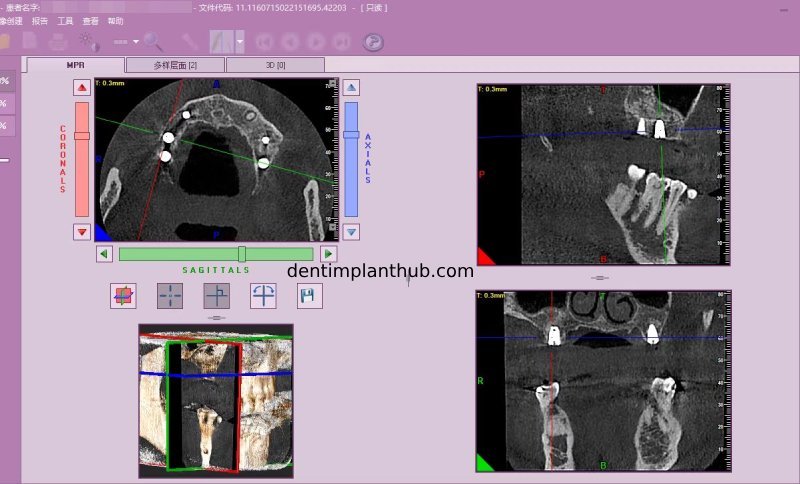

Screenshot of repeat CT on 7/1/25